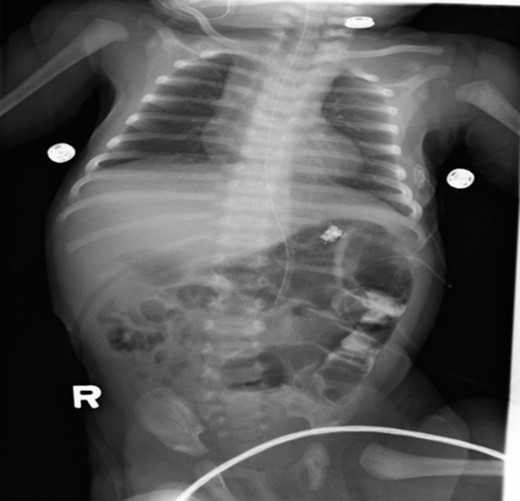

A 1-day-old baby girl, born by normal spontaneous vaginal delivery, was evaluated for abdominal distension and history of having not passed meconium. An abdominal X-ray was suspicious for malrotation (Fig. 1). The patient did not have any evidence of sepsis. An echocardiogram ruled out any congenital cardiac anomalies.

Pre-operative abdominal x-ray showing a gastric and duodenum distention with paucity of small bowel gas distally, suggesting duodenal atresia and malrotation.